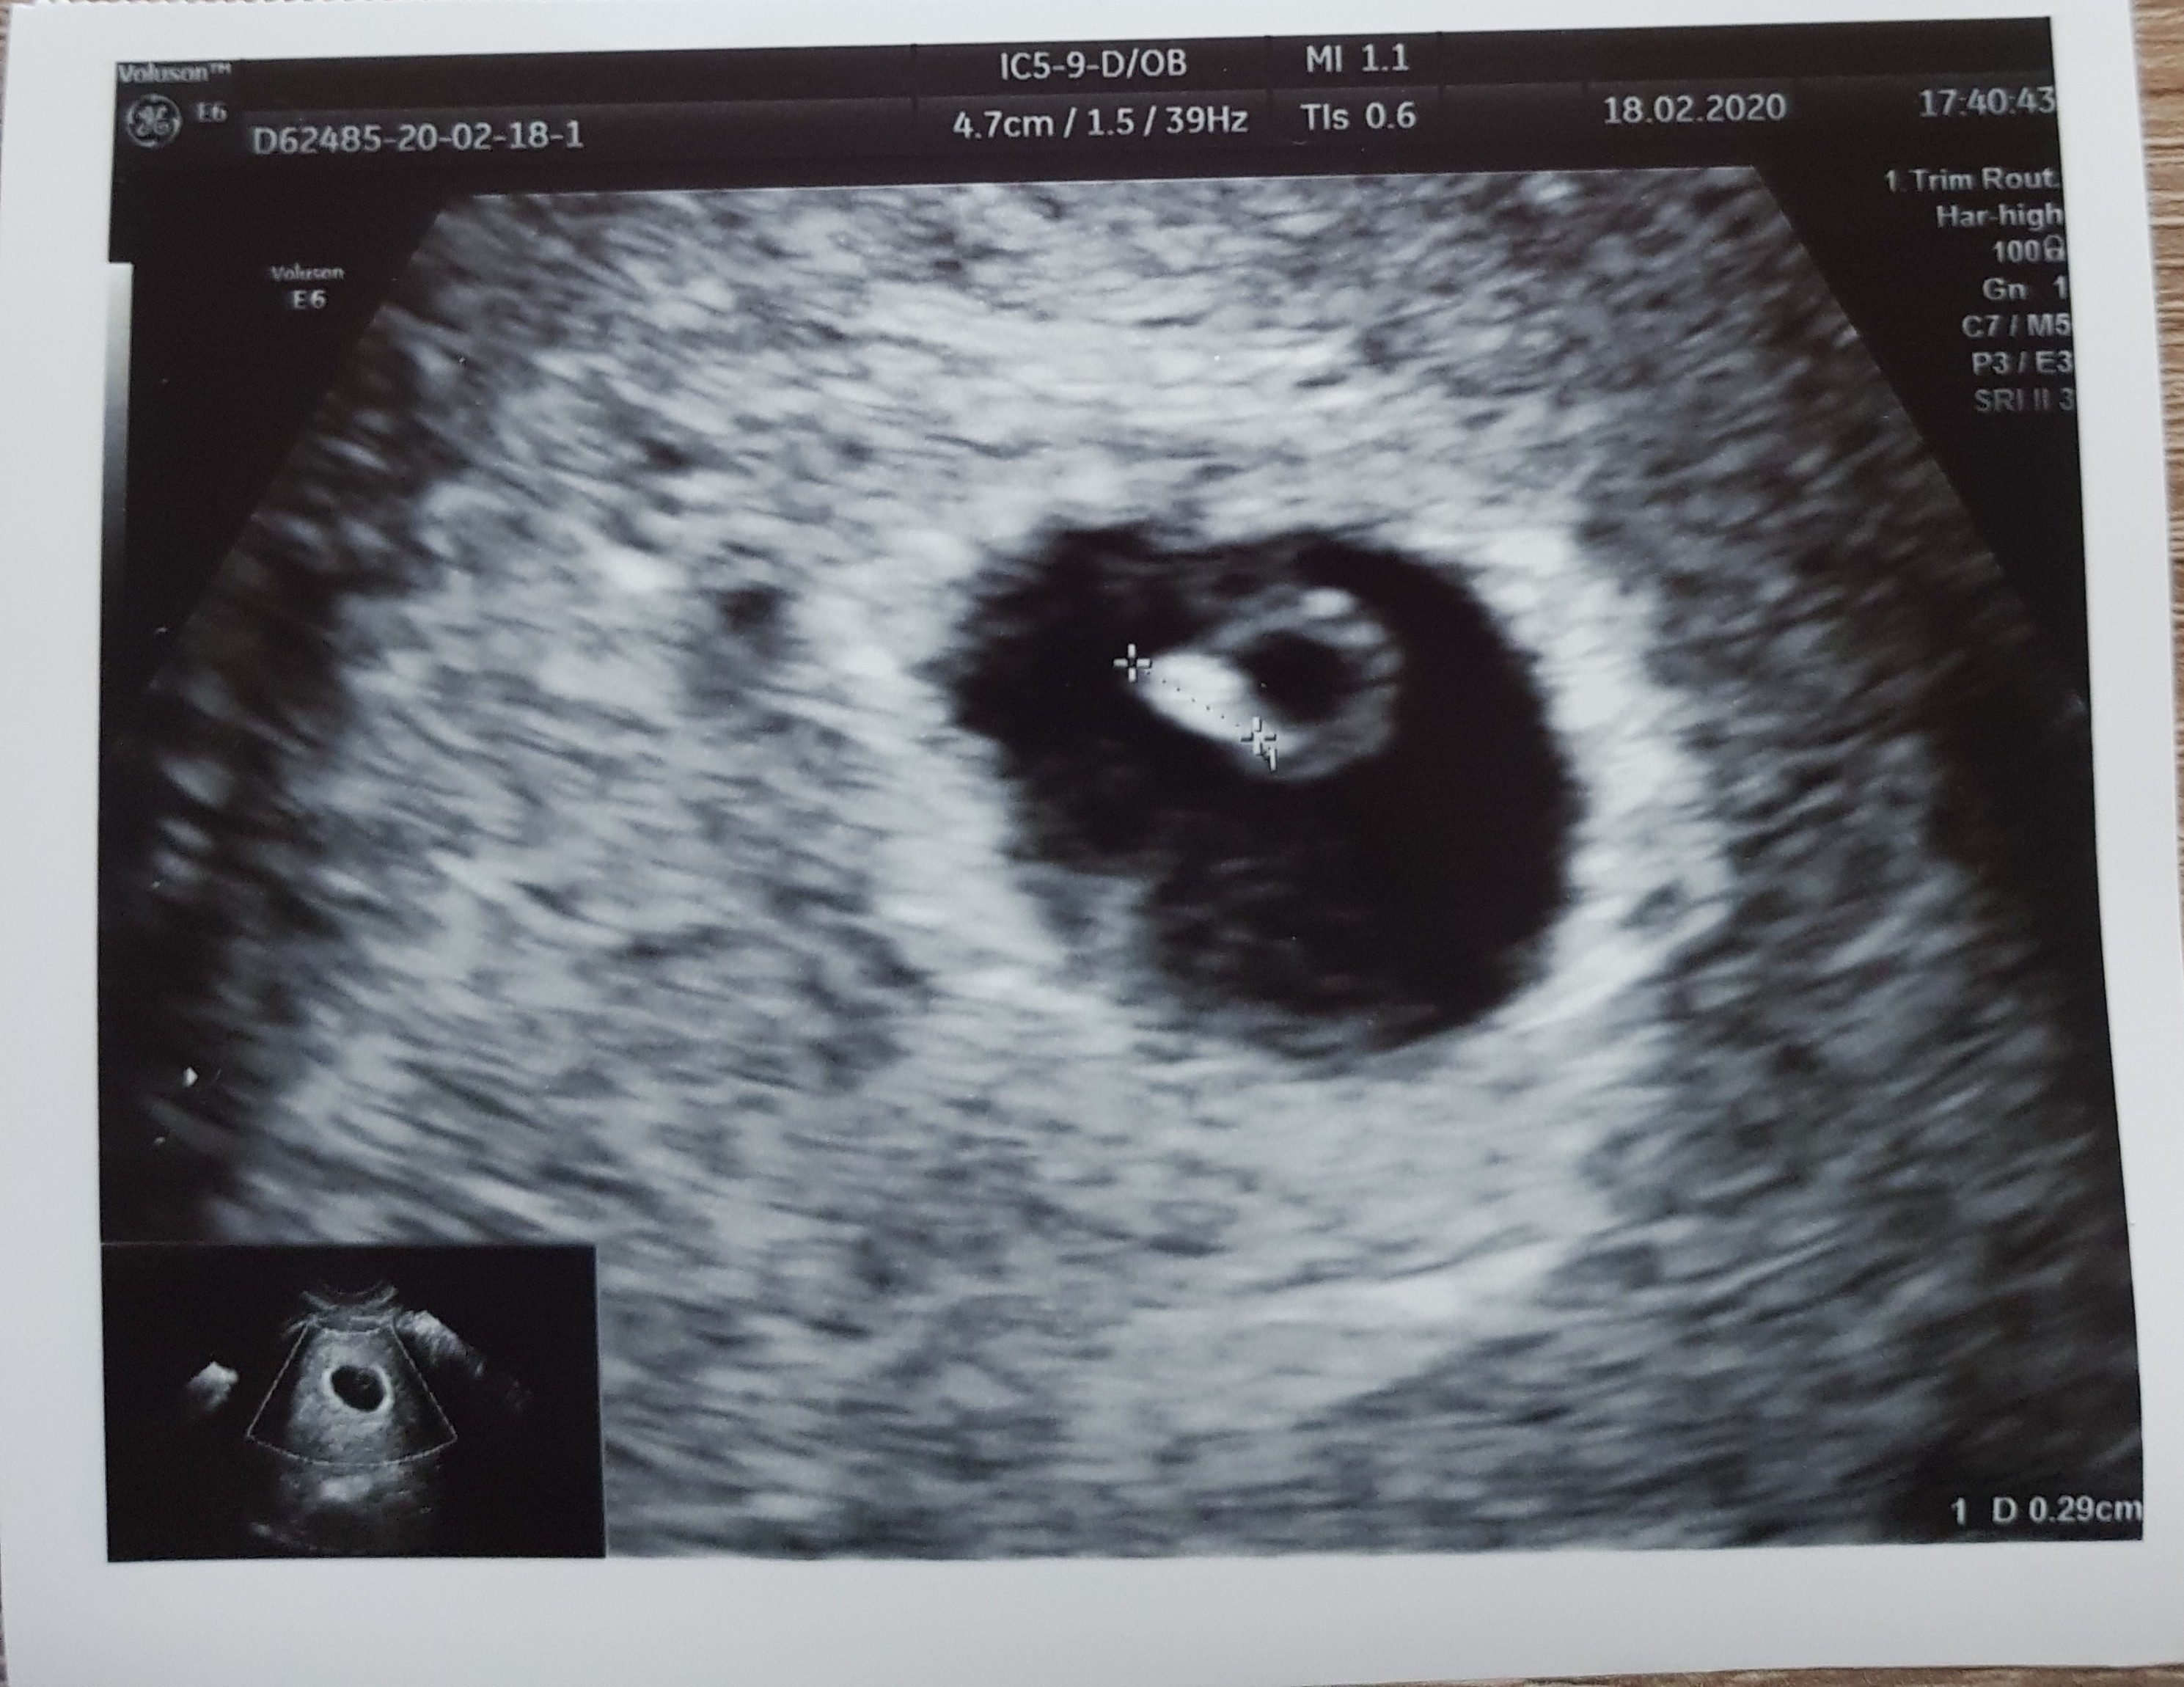

My też już po wizycie ❤ co prawda serduszko jeszcze nie bije- ciąża o wiele młodsza niż wychodziłoby z terminu ostatniej @- ale tego się spodziewałam, bo cykle nieregularne, następna wizyta w przyszły czwartek, liczymy że usłyszymy ❤, dzidzia ma prawie 3 mm- przełom 5/6 tygodnia. Dostałam progesteron, zwiększamy dawkę Euthyroxu- jutro idę na badania plus krzepliwość bo wcześniej miałam z nią problemy.

My też już po wizycie [emoji173] co prawda serduszko jeszcze nie bije- ciąża o wiele młodsza niż wychodziłoby z terminu ostatniej @- ale tego się spodziewałam, bo cykle nieregularne, następna wizyta w przyszły czwartek, liczymy że usłyszymy [emoji173], dzidzia ma prawie 3 mm- przełom 5/6 tygodnia. Dostałam progesteron, zwiększamy dawkę Euthyroxu- jutro idę na badania plus krzepliwość bo wcześniej miałam z nią problemy.